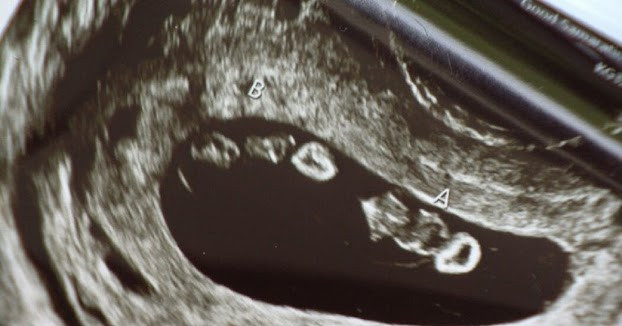

Hình ảnh siêu âm phát hiện 4 thai nhi trong bụng người mẹ.

Lần siêu âm tiếp theo càng khiến tất cả kinh ngạc hơn khi kỹ thuật viên siêu âm phát hiện không chỉ một mà đến 2 cặp song sinh đang lớn lên trong bụng Ashley. "Lúc đó, cô ấy đã phải xin ra ngoài tra cứu thêm thông tin vì không tin vào những gì mình vừa nhìn thấy. Khi quay lại, cô ấy nói với tôi rằng tôi đang mang thai 2 cặp song sinh. Tôi thực sự sốc!" – Ashley chia sẻ.